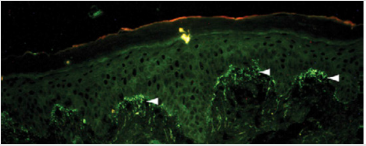

When a histopathological examination is sufficient to provide clues to the diagnosis of dermatitis herpetiformis, other conditions such as linear immunoglobulin A bullous dermatosis (LABD) and bullous lupus erythematosus, can reveal a histopathological appearance which is also similar to dermatitis herpetiformis. Therefore, immunofluorescence examination is an examination that is also important for definitive diagnosis. The accumulation of granular IgA at the papillary end of the dermis in Figure 3 is a pathognomonic feature of dermatitis herpetiformis (when compared with the linear pattern of IgA buildup seen in LABD). IgA accumulation in dermatitis herpetiformis is thought to be polyclonal but mostly consists of IgA1. Occasionally granular build-up along the basement membrane occurs in dermatitis herpetiformis, which can be misdiagnosed as LABD [10,11].

Figure 3: Immunofluorosence of dermatitis herpetiformis. Direct immunofluoscence in perilesion skin shows IgA deposit in dermal papilar [11].